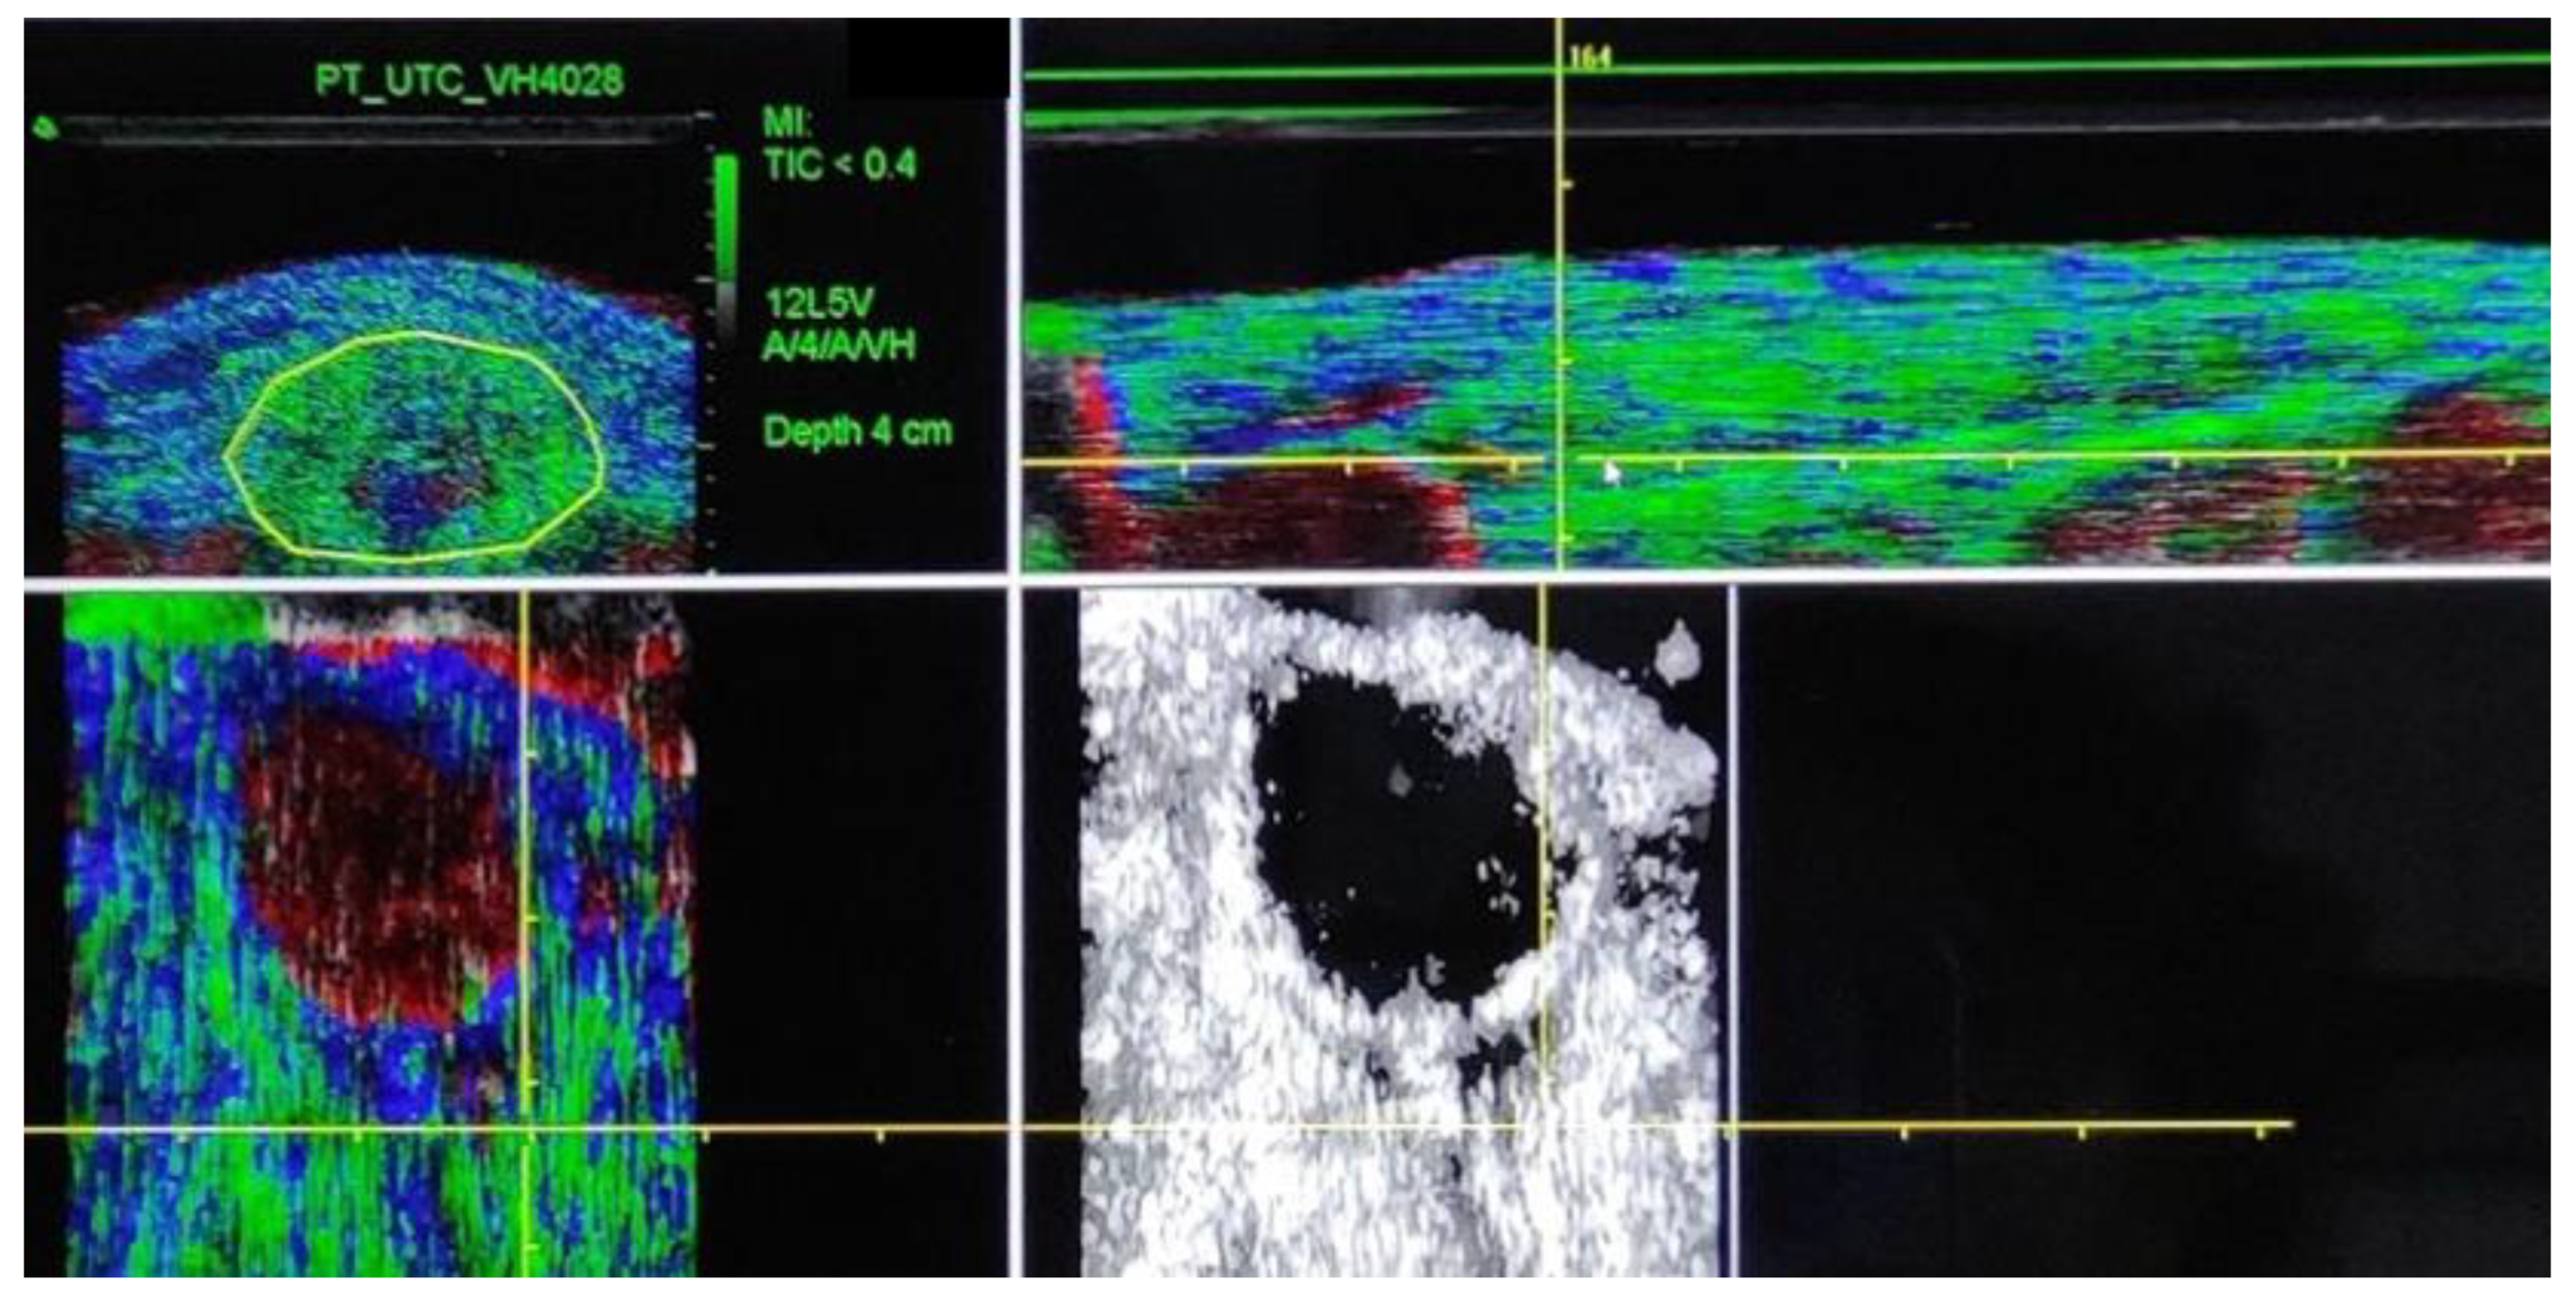

2.2. Procedure